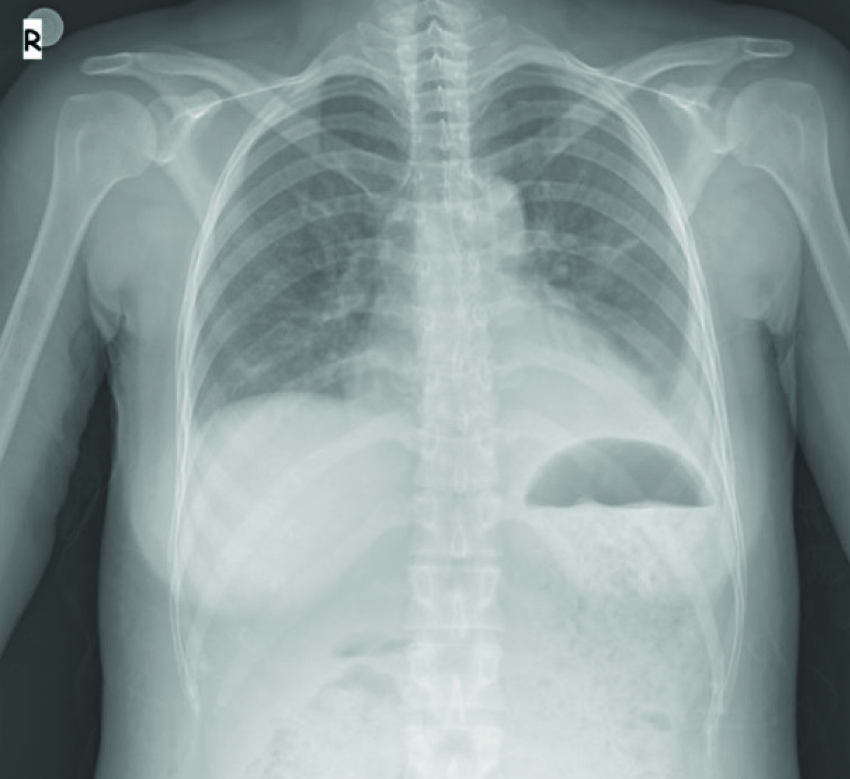

A 27-year-old primigravid female was referred to our clinic with severe preeclampsia at 35 weeks of gestation. Her medical history was uneventful. She was administered 1000 mg/day alpha-methyldopa since, 28 weeks of gestation. On admission, her blood pressure was 180/ 110 mmHg and urinary albumin 2+. Complete Blood Count (CBC) was in normal limits. Her serum biochemical analysis revealed: ALT: 401 U/L, AST: 292 U/L, creatinine: 1.39 mg/dL, urea: 40 mg/dL (16.6-48.5), uric acid: 8 mg/dL (2.4-5.7), total protein: 6.25 g/dL (6.4-8.3) and albumin: 3.3 g/dL (3.5-5.2). Her coagulation profile was within normal limits. A single live fetus of 31 weeks gestation along with 85 mm amniotic fluid index was detected by USG. Colour flow doppler USG revealed increased umbilical artery resistance. There were no subjective symptoms such as headache, epigastric pain and visual symptoms. Late decelerations were detected on cardiotocography trace and she was diagnosed to have fetal distress. An emergency cesarean section was performed and 1450 gm male fetus was delivered with APGAR score of 8/10. Postoperatively, she was given amlodipine 20 mg/day. Her blood pressure recordings were within normal limits. On first postoperative day 20-30 cc/hour urine output was detected. Serum transaminases were lowered. On the second postoperative day, she had abdominal distension and severe abdominal pain. The USG showed minimal ascites fluid. CBC was normal and serum albumin level was 2.5 gm/dl. Serum sodium level was normal. She had 320 μg albumin/mg creatinine (albumin:creatinine ratio) on spot urine sample. On the 3rd post-operative day, her abdominal distension increased and USG revealed massive ascites. Abdominal drainage was performed and albumin infusion was administered. Approximately 3000 cc serous fluid was drained. The sample analysis revealed as characteristic of transudate. Abdominal distension regressed but she had pulse of 130/min. X-ray chest showed bilateral minimal pleural effusion [Table/Fig-1]. She had normal echocardiography. Serum creatinine levels regressed (<1 mg/dL) but her urine output exceeded 500 cc/hour. IV hydration was adjusted as less than 1000 cc of total daily urine output. On post-operative day 4, she still had abdominal distension and concomitant respiratory distress. Computed Tomography showed bilateral pleural effusion and minimal ascites and atrophic right kidney [Table/Fig-2,3]. In spite of increased urine output her sodium level remained within normal levels. There was no proteinuria in spot urine sample. On post-operative day 5, she had total of 3000 cc/day hydration and 5000 cc/day urine output. Her complaint regressed on the following days and on post-operative day 7 USG showed no ascites and gap between input and output disappeared. She was discharged on postoperative day 10.

X-ray chest, postpartum day 3, bilateral minimal pleural effusion.